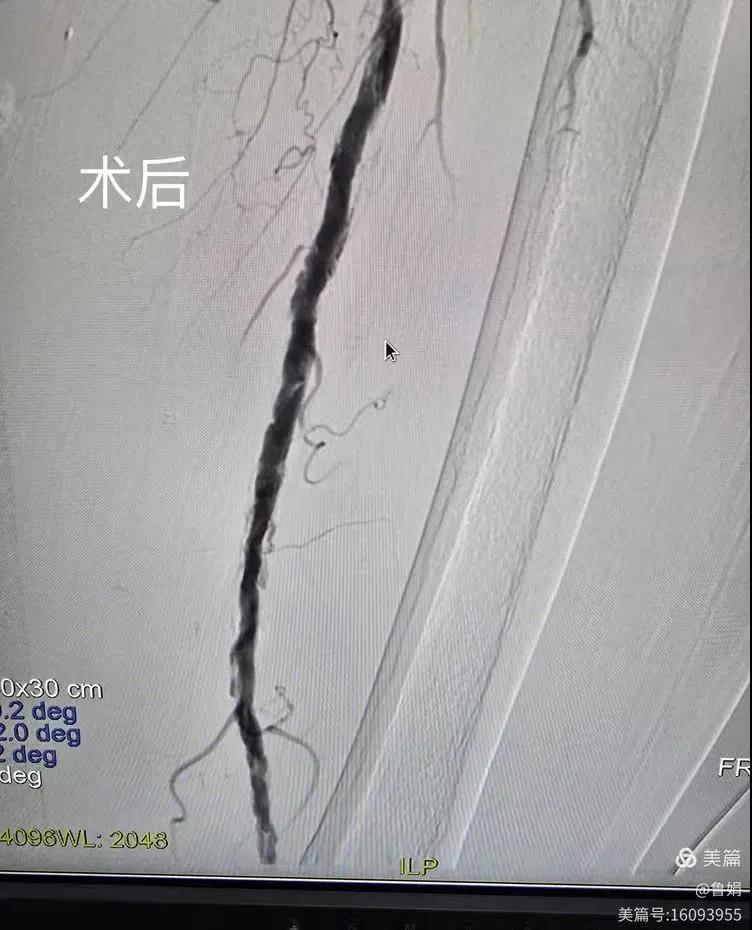

據(jù)悉,該患者,女,73歲,下肢動(dòng)脈硬化閉塞癥,“以靜息痛,間歇性跛行”入院,CTA評(píng)估:股淺動(dòng)脈,腘動(dòng)脈間斷性多段重度狹窄,外二科血管外科團(tuán)隊(duì)根據(jù)患者病情,結(jié)合檢查結(jié)果,經(jīng)過科室會(huì)診后,決定對(duì)該病人行介入治療。手術(shù)由周創(chuàng)業(yè)副主任與北大一院血管外科專家郭宏杰教授聯(lián)合開展,對(duì)股淺動(dòng)脈,腘動(dòng)脈重度閉塞段行血管開通+藥涂球囊擴(kuò)張成形,術(shù)后狹窄明顯緩解,血流恢復(fù)!

下肢動(dòng)脈閉塞的介入開通是外周介入領(lǐng)域難度最大的技術(shù)之一,這項(xiàng)微創(chuàng)介入手術(shù)的開展,實(shí)現(xiàn)了漯河市中醫(yī)院在下肢動(dòng)脈血管介入治療上零的突破,進(jìn)一步推動(dòng)了醫(yī)院介入治療技術(shù)的發(fā)展,讓患者足不出戶就能切實(shí)享受到優(yōu)質(zhì)的醫(yī)療資源,極大方便了患者就醫(yī)。(介入中心:魯娟)